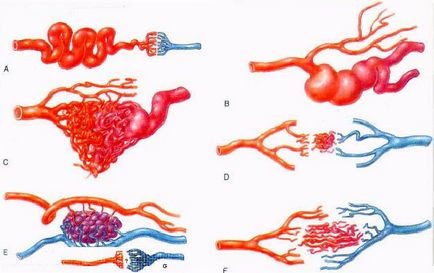

A típusú vaszkuláris fejlődési rendellenességek:

B) arteriovénás fistular

C) arteriovenosus ratsemoznaya (75%)

D) arteriovénás mikromalformatsiya

E) arteriovenosus barlangos (11%)

F) telangiectasia

G) Vénás